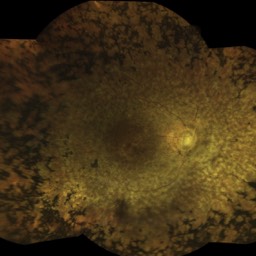

Quelques pathologies ophtalmologiques de la rétine

Ci-dessous on voit des néovaisseaux dus à une Dégénérescence Maculaire Liée à l'Age (DMLA). Les rétinophotographies sont réalisées avec l'appareil Eidon de la société italienne CenterVue, et l'OCT angiography est réalisée avec l'OCT de la société américaine Optovue.

Déplacez à la souris la tirette vers la gauche ou la droite, ce qui permet de comparer la vue en couleurs et l'emplacement des néovaisseaux choroidiens.